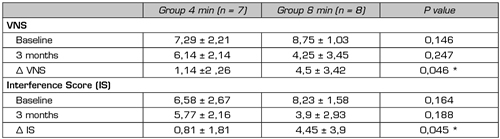

We did not find any studies comparing different schemes of exposure to PRF. In our department, a prospective, randomized, double-blind study is currently being conducted in patients with lumbosacral radicular pain refractory to epidural steroids, using as a control group the application of the exposure time to PRF that we consider as standard, that is, 2 cycles of 120 seconds (4 minutes) and as a study group, the application of 4 cycles of 120 seconds each (8 minutes). Preliminary results of the 15 patients performed (8 patients in the 8-minute group and 7 patients in the control group) show a decrease in VNS and pain interference in daily activities in both groups, being the differences between baseline and at 3-month assessments larger in the 8-minute group. Despite the low sample size, these differences reached statistical significance (Surbano and Castroman, unpublished data) (Table III). This would indicate a more powerful analgesic effect of PRF when applied for longer periods, this effect could be maintained for at least 3 months after the single application of the procedure.

Table III. Assessment of pain intensity with the verbal numeric scale (VNS) and pain interference in daily activities (Interference Score, IS) using Brief Pain Inventory in patients with unilateral lumbosacral radicular pain, in whom it was applied, in a randomized manner, 4 or 8 minutes of pulsed radiofrequency of the dorsal root ganglion. The evaluation was performed at baseline and at 3 months, differences between baseline values and at 3 months (Δ VNS and Δ IS) were also presented